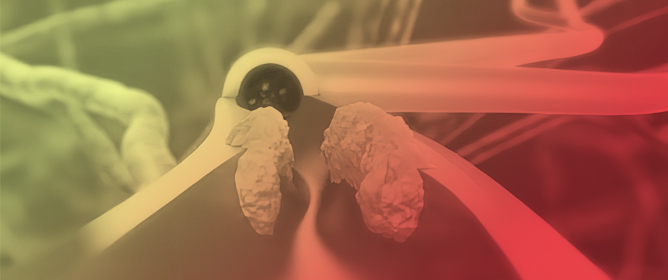

The Middle Meningeal Artery (MMA) occupies a pivotal role in the pathophysiology of migraine, functioning as a vascular and neuroimmune interface that precipitates the characteristic pulsatile pain. The inhibition of this pathophysiological cascade has been investigated as a therapeutic strategy. However, fewer than a dozen centers globally have disseminated procedural or mechanistic data. Given the nascency of this field and the imperative for standardization, the present review synthesizes mechanistic and clinical evidence underpinning intra-arterial pharmacological modulation of the MMA for migraine management. Methods: A focused narrative review was undertaken, drawing upon select but influential studies from pioneering research groups investigating intra-arterial interventions targeting the MMA. The extant literature was thematically categorized and organized according to the loci of cascade interruption and their corresponding clinical outcomes. Results: Since 2009, intra-arterial therapies for severe headache syndromes have evolved, initially utilizing nimodipine for vasospasm-related headaches, progressing to verapamil for reversible cerebral vasoconstriction, and more recently, lidocaine for refractory or status migrainosus, occasionally in conjunction with MMA embolization. Contemporary research uses language that conceptualizes migraine as an immunologically mediated neurovascular disorder, as opposed to a purely vascular or neuronal entity. Recent investigations have identified interleukins such as Interleukin-1β, Tumor Necrosis Factor-α, and Interleukin-6 as critical amplifiers of trigeminovascular activation. Purinergic signaling through the P2X3 receptor and the P2Y13 receptor, in conjunction with pituitary adenylate cyclase-activating polypeptide and vasoactive intestinal peptide pathways, has been implicated in the modulation of MMA excitability and neuropeptide release. The development of novel calcitonin gene-related peptide receptor antagonists, such as zavegepant, further substantiates the artery’s significance as a pharmacological target. Conclusions: These findings support a shift toward immune-modulating intra-arterial therapeutic strategies, with migraine interventions targeting cytokine and neuroimmune signaling within the MMA, rather than relying exclusively on vasodilatory mechanisms.

![Pathophysiology of migraine within the trigeminovascular system. (1) Mechanical dilation of the MMA increases Intercellular Adhesion Molecule 1 (ICAM-1) and Vascular Cell Adhesion Molecule 1 (VCAM-1) which support immune cell recruitment. It also activates perivascular trigeminal nociceptors, (2) leading to action potential propagation and calcium-dependent neuropeptide release. (3) Released mediators amplify migraine signaling through vascular and inflammatory pathways. Calcitonin-Gene Related Peptide (CGRP) and Neurokinin A mediate vasodilation, while Substance P causes mast cell activation. The substances released from mast cells have a variety of roles. Important for the pathophysiology presented, is that Tumor Necrosis Factor (TNF) alpha and Interleukin-6 (IL-6) increase CGRP release and C-C motif Chemokine Ligand 2 (CCL2) stimulates immune cell recruitment and neuronal CGRP reactivity, further amplifying the pathway [13]. Substance P may also be released by mast cells in certain disease states [13]. (4) These processes result in endothelial disruption with plasma extravasation (5) and edema-driven nociceptor sensitization [16]. Pharmacologic agents interrupt the cascade at discrete neurovascular nodes, with Lidocaine acting at sodium (Na+) channels and Calcium channel blockers acting at both nerve endings and plasma membrane of mast cells.](https://mdpi-res.com/cdn-cgi/image/w=470,h=317/https://mdpi-res.com/jvd/jvd-05-00009/article_deploy/html/images/jvd-05-00009-g001-550.jpg)